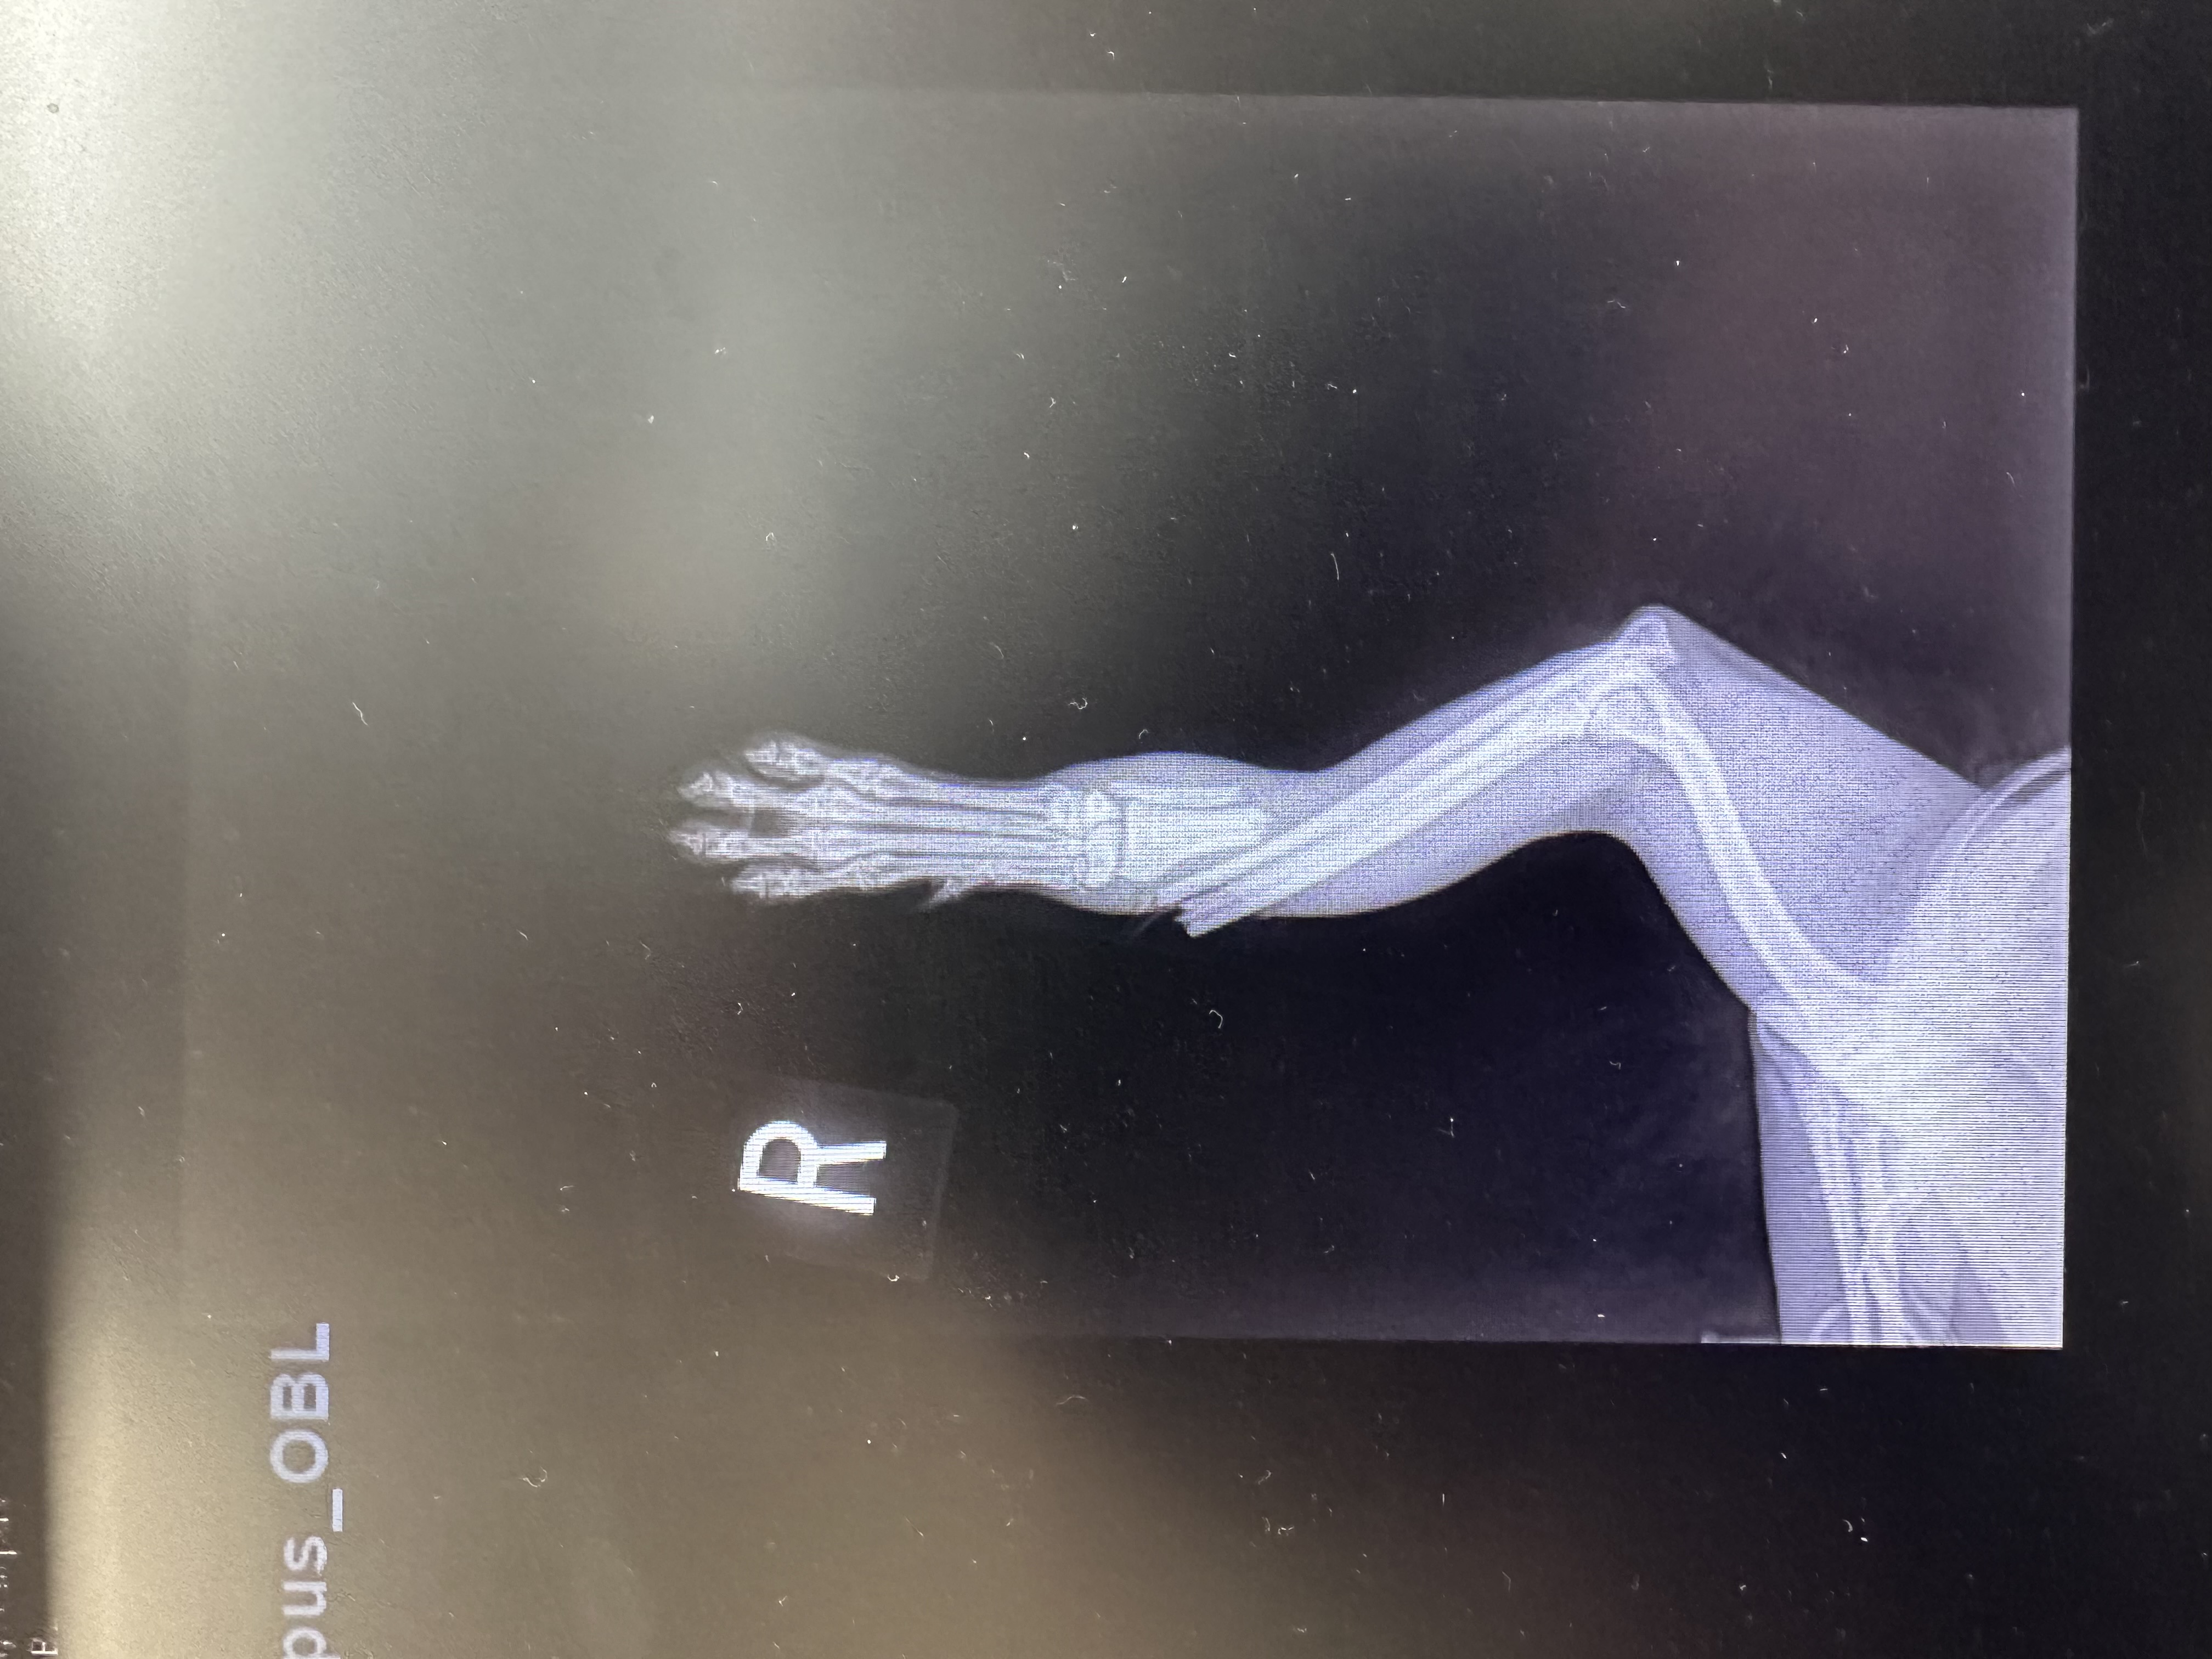

Elli’s owner gave News 12 the videos, as well as the animal’s x-ray, and says the dog suffered a broken leg that required amputation.

“I am absolutely devastated. I knew her ten years. Someone I trusted with my entire heart did this to my baby,” says the woman.